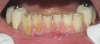

Figure  3  Severe dental erosion and attrition in a GERD patient.

Figure 3

Figure  5  Loss of tooth surface and yellowing of teeth in a young patient with untreated GERD.

Figure 5